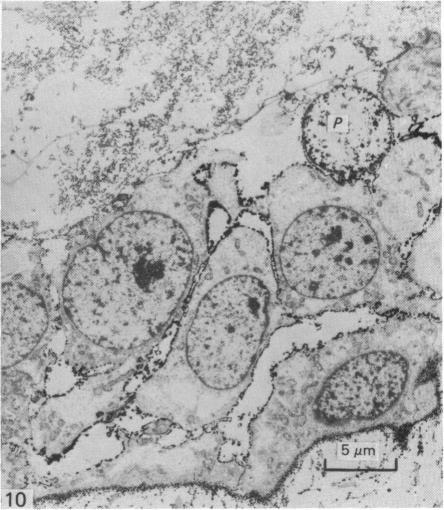

The permeability of the epithelium of the skin of fetal rats demonstrated with a lanthanum-containing solution.

The permeability of the skin of fetal rats between 14 and 21 days of intrauterine life was investigated by injecting lanthanum nitrate solution subepidermally and by exposing the external surface of other fetuses to the same solution. Up to the age of 18 days, the epidermis was freely permeable from the basal surface and lanthanum entered junctional complexes between periderm cells. After 18 days, the limit of permeation corresponded to the level at which membrane-coating granules were released into the intercellular spaces. At all ages, permeation from the outer surface was limited to the junctional complexes between the periderm cells covering the epidermis throughout fetal life. Damage to the periderm at early ages resulted in complete penetration of the epidermis by lanthanum. It was concluded that, prior to secretion of the epidermal permeability barrier at 18 days, the periderm was the principal barrier to permeation by lanthanum.